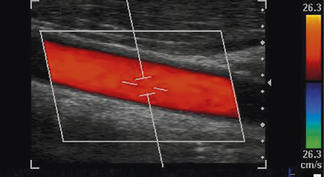

Many peripheral vessels run parallel to the face of a linear transducer and perpendicular to the Doppler beam. If the angle of the Doppler beam with respect to the vessel is at 90°, little or no Doppler signal will be detected, as seen in Figure 11.12. When using a linear array transducer the operator is able to overcome this problem by electronically steering the Doppler beam. This is performed by altering the angle of the color box, as illustrated in Figure 11.13. The objective is toobtain a sufficiently small angle between the Doppler beam and blood vessel to provide reliable Doppler signals.

image

Fig. 11.13 Color flow image of the common carotid artery with a steered color box to obtain sufficient angles for reliable Doppler signals

In practice, an experienced operator alters the scanning approach and steers the Doppler beam to obtain good angles between the Doppler beam and vessel to avoid unambiguous color flow images.